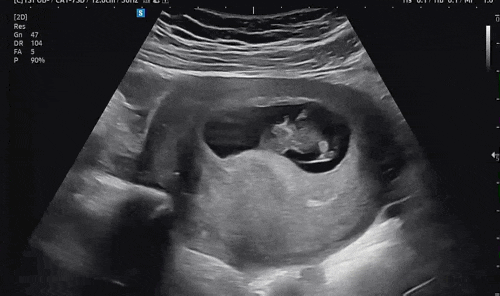

둘째일기 다섯번째 6주-12주 기록

아기집 이후로 포스팅이 없다니 ㅎㅎㅎ 그동안 입덧으로 지옥을 오갔다 입덧약 4알씩 꽉 채워 먹어도 입덧...